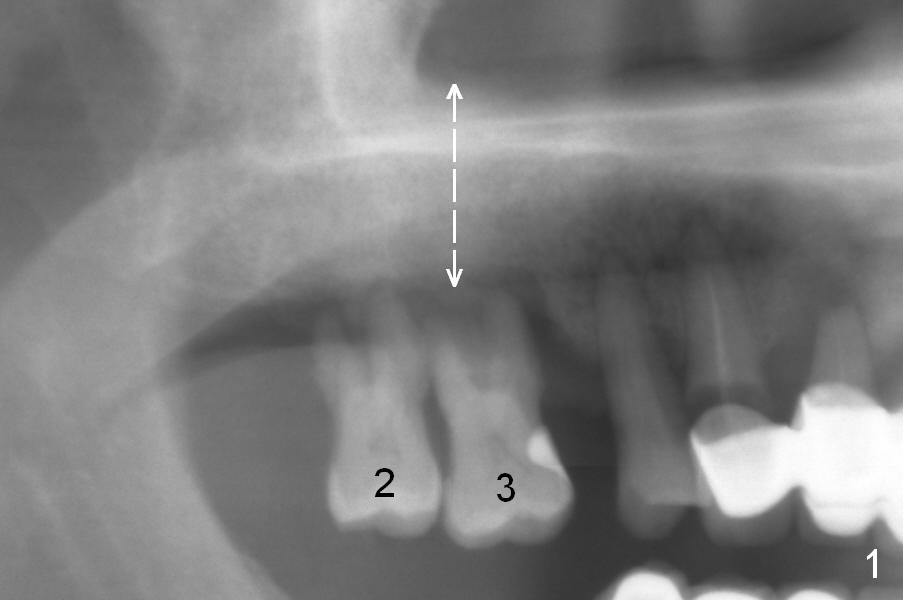

The maxillary 1st molar has 3 widely separated roots (Fig.1-3: #3) with a wide septum in between, as compared to the 2nd one (#2). The septum is a suitable site of immediate implant. When the septum is destroyed by pathology, the immediate implant has to be big.

By comparing the root morphology of an extracted tooth (Fig.7,8: #15) with that of X-ray (Fig.9) repeatedly, we can develop an ability to visualize the septum prior to surgery.